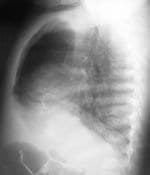

Figura 1. Radiografía convencional (A-P y lateral). Imagen radiolúcida apical derecha por sobreinsuflación del lóbulo superior,

evidenciada por la posición de la linea de unión mediastinal anterior. Compresión del parénquima pulmonar del lóbulo medio.